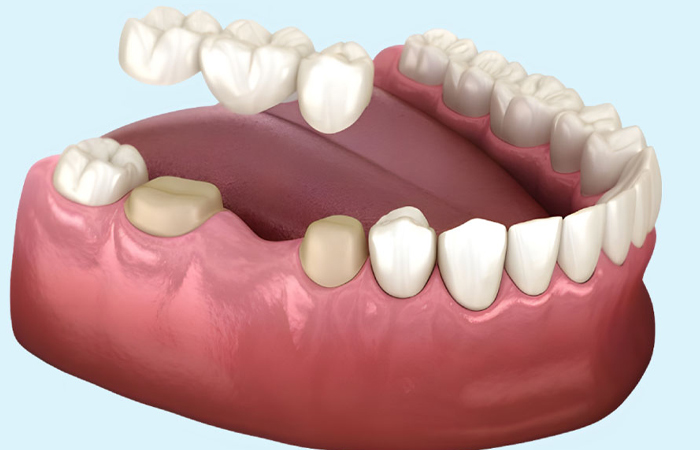

بریج دندان یک روش ترمیمی دندانی است که برای پر کردن فضاهای خالی بین دندانها به کار میرود.

زمانی که یک یا چند دندان از دست رفته باشند،

بریج دندان به عنوان یک پل از دندانهای مجاور به دندانهای از دست رفته متصل میشود و این فضا را پر میکند.

بریج معمولاً از چند دندان مصنوعی به هم پیوسته تشکیل میشود که یک یا چند دندان مصنوعی در وسط قرار دارد

و توسط دندانهای سالم در طرفین آن نگهداری میشود.

این دندانهای سالم به عنوان پایه برای بریج عمل میکنند و معمولاً در کنار آنها ترمیمهایی مانند

تاج دندان برای استحکام بیشتر انجام میشود.

عملکرد بریج به این صورت است که از طریق اتصال دندانهای مصنوعی به دندانهای سالم،

به بهبود ظاهر، عملکرد جویدن و صحبت کردن بیمار کمک میکند.

این روش میتواند احساس راحتی و طبیعی بودن را برای بیمار ایجاد کند و به حفظ سلامت دهان و دندانها کمک کند.